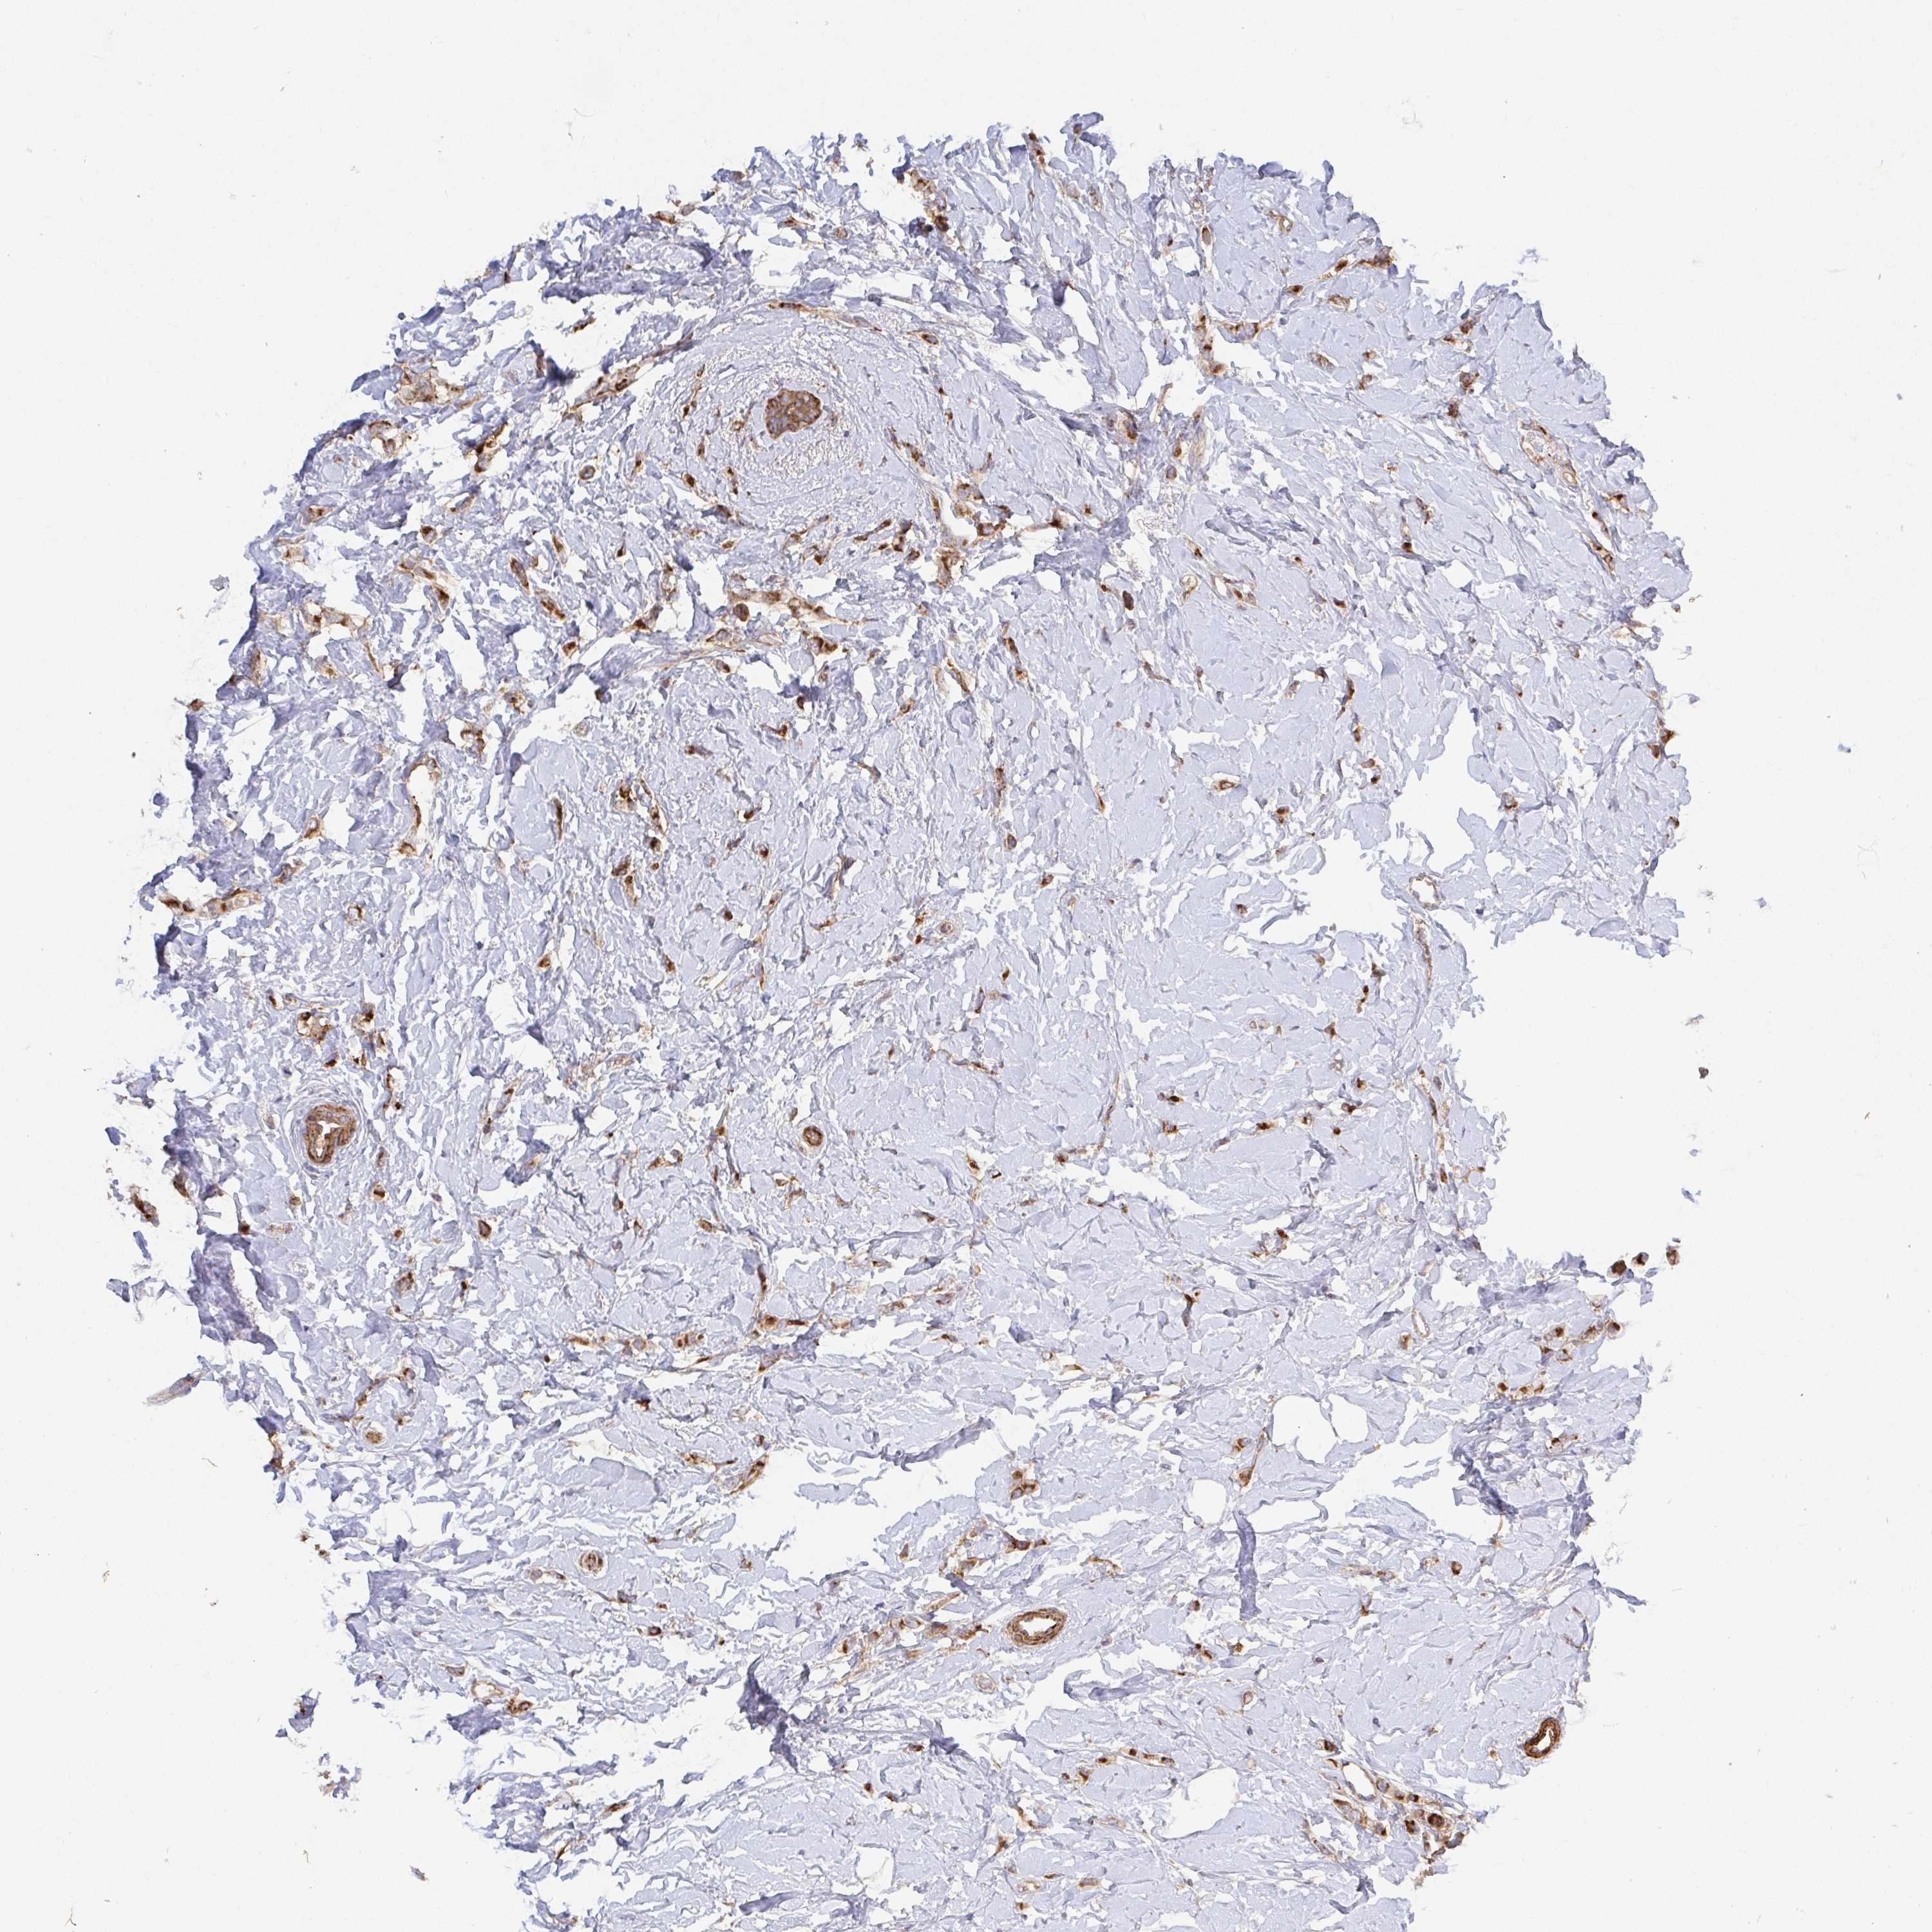

CANCER BREAST CANCER Show tissue menu

BRCA TCGA BRCA VALIDATION PROTEIN EXPRESSION

Breast cancer

Human cancer